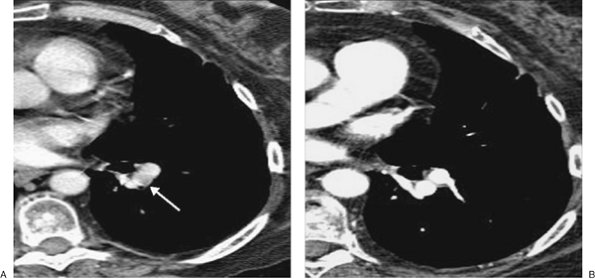

FIGURE 17-3. Acute PE. A: CTPA of a 77-year-old man with shortness of breath shows an intraluminal filling defect, surrounded by a rim of contrast, within the right lower lobe segmental pulmonary arteries (arrow). B: Coronal CTPA shows decreased caliber of arteries in the right lung compared with the left and filling defect within right lower lobe vessels. C: Catheter-based pulmonary angiogram confirms clot within right lower lobe vessels (arrows).

FIGURE 17-4. Acute PE. A: CTPA of a 77-year-old woman with a gastrointestinal bleed and DVT shows an intraluminal filling defect in a left lower lobe segmental pulmonary artery (arrow). B: CTPA at a more superior level shows intraluminal filling defects, surrounded by contrast material, in the right middle lobe and left lower lobe pulmonary arteries (arrows). C: CTPA at a level superior to (B) shows an intraluminal filling defect, surrounded by a thin rim of contrast material, in a right lower lobe segmental pulmonary artery (arrow).

FIGURE 17-5. Acute PE. A: CTPA of a 78-year-old woman shows an intraluminal filling defect surrounded by contrast material in the proximal right lower lobe pulmonary artery (arrow). B: Coronal CTPA shows that the intraluminal filling defect extends from the proximal right lower lobe pulmonary artery inferiorly to distal branches (arrows). C: CTPA with lung windowing shows oligemia and diminution of vessels on the right (Westermark sign).